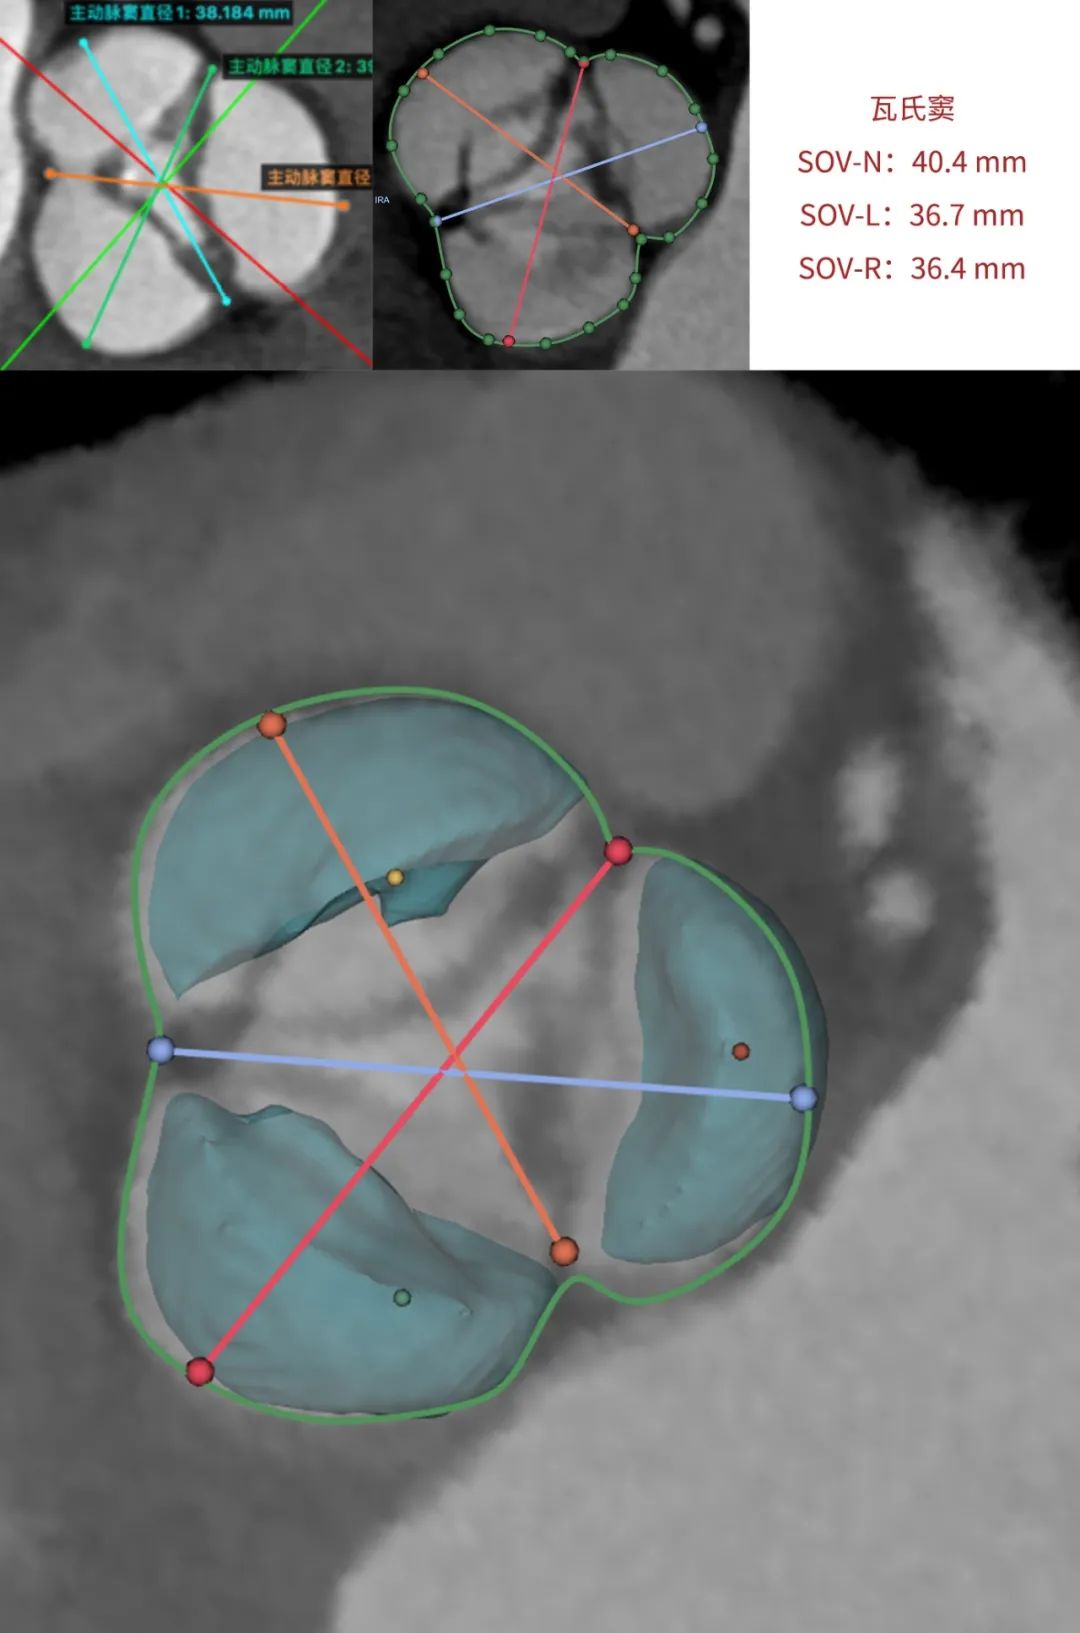

患者为68岁男性,因心悸胸闷入院。术前超声报告显示,患者为功能型二叶式主动脉瓣,右无融合钙化,主动脉瓣明显增厚钙化,瓣叶开放受限,主动脉瓣前向血流加速Vmax=4.2m/s,平均跨瓣压差36mmHg,有效开口面积0.7cm²,舒张期瓣口中度反流信号。

临床团队同时使用了基于医生手工描点的围术期影像评估软件和基于人工智能的瓣膜疾病围术期分析辅助决策软件进行术前影像学评估。

通过术前测量,对病例深入分析,结合人工智能术前分析辅助决策软件进行三维和二维图像融合,郭应强教授指出本例手术存在以下难点:

功能型二叶式主动脉瓣,瓣叶开口偏向一侧,瓣膜释放后存在不同轴可能。

选择植入Xcor-26瓣膜,充分利用支撑臂避免瓣膜移位发生。

标准位释放,双锚定实现生理性同轴以获得更优的血流动力学效果。

在LAO 9 CAU 24(左右窦重合体位)投照角度,瓣叶交界贴合释放。